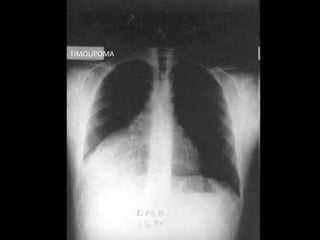

MEDIASTINO ANTERIOR

TIMOMA

TERATOMA

LIPOSARCOMA

LINFOMA

BOSIO

TIMOLIPOMA

SEMINOMA